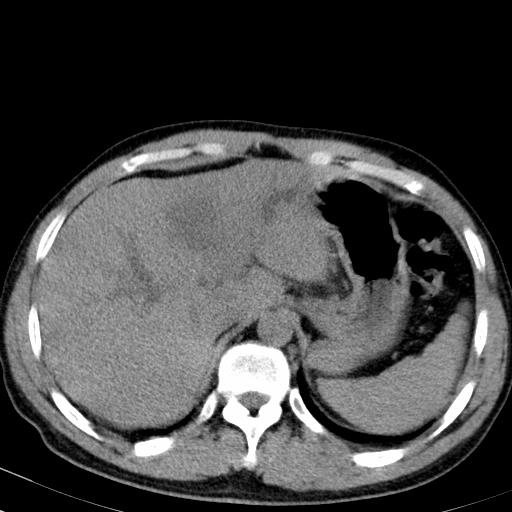

患者上腹部疼痛一月余,伴巩膜黄染;

实事求是的说,强化效果很一般,重点部位应重点观察,但有一点可以明确:肝门部胆管细胞癌。

考虑肝左叶胆管细胞癌侵犯肝门区并肝内胆管及肝总管扩张。

肝左叶肿块清度增强,所在的叶胆管扩张。考虑胆管细胞癌。

考虑肝左叶胆管细胞癌侵犯肝门区并肝内胆管及肝总管扩张、肝门淋巴结肿大。